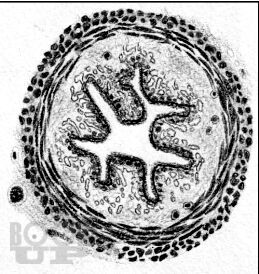

В предлагаемом учебном пособии, состоящем из 7 разделов, представлены сведения о последовательности развития и гистологическом строении органов ротовой полости человека. Для каждого раздела обозначена цель, вопросы для самостоятельной подготовки, представлен информационный блок, описание микропрепаратов. С целью самоконтроля приводится перечень тестовых заданий, ситуационных задач и ответы на них.